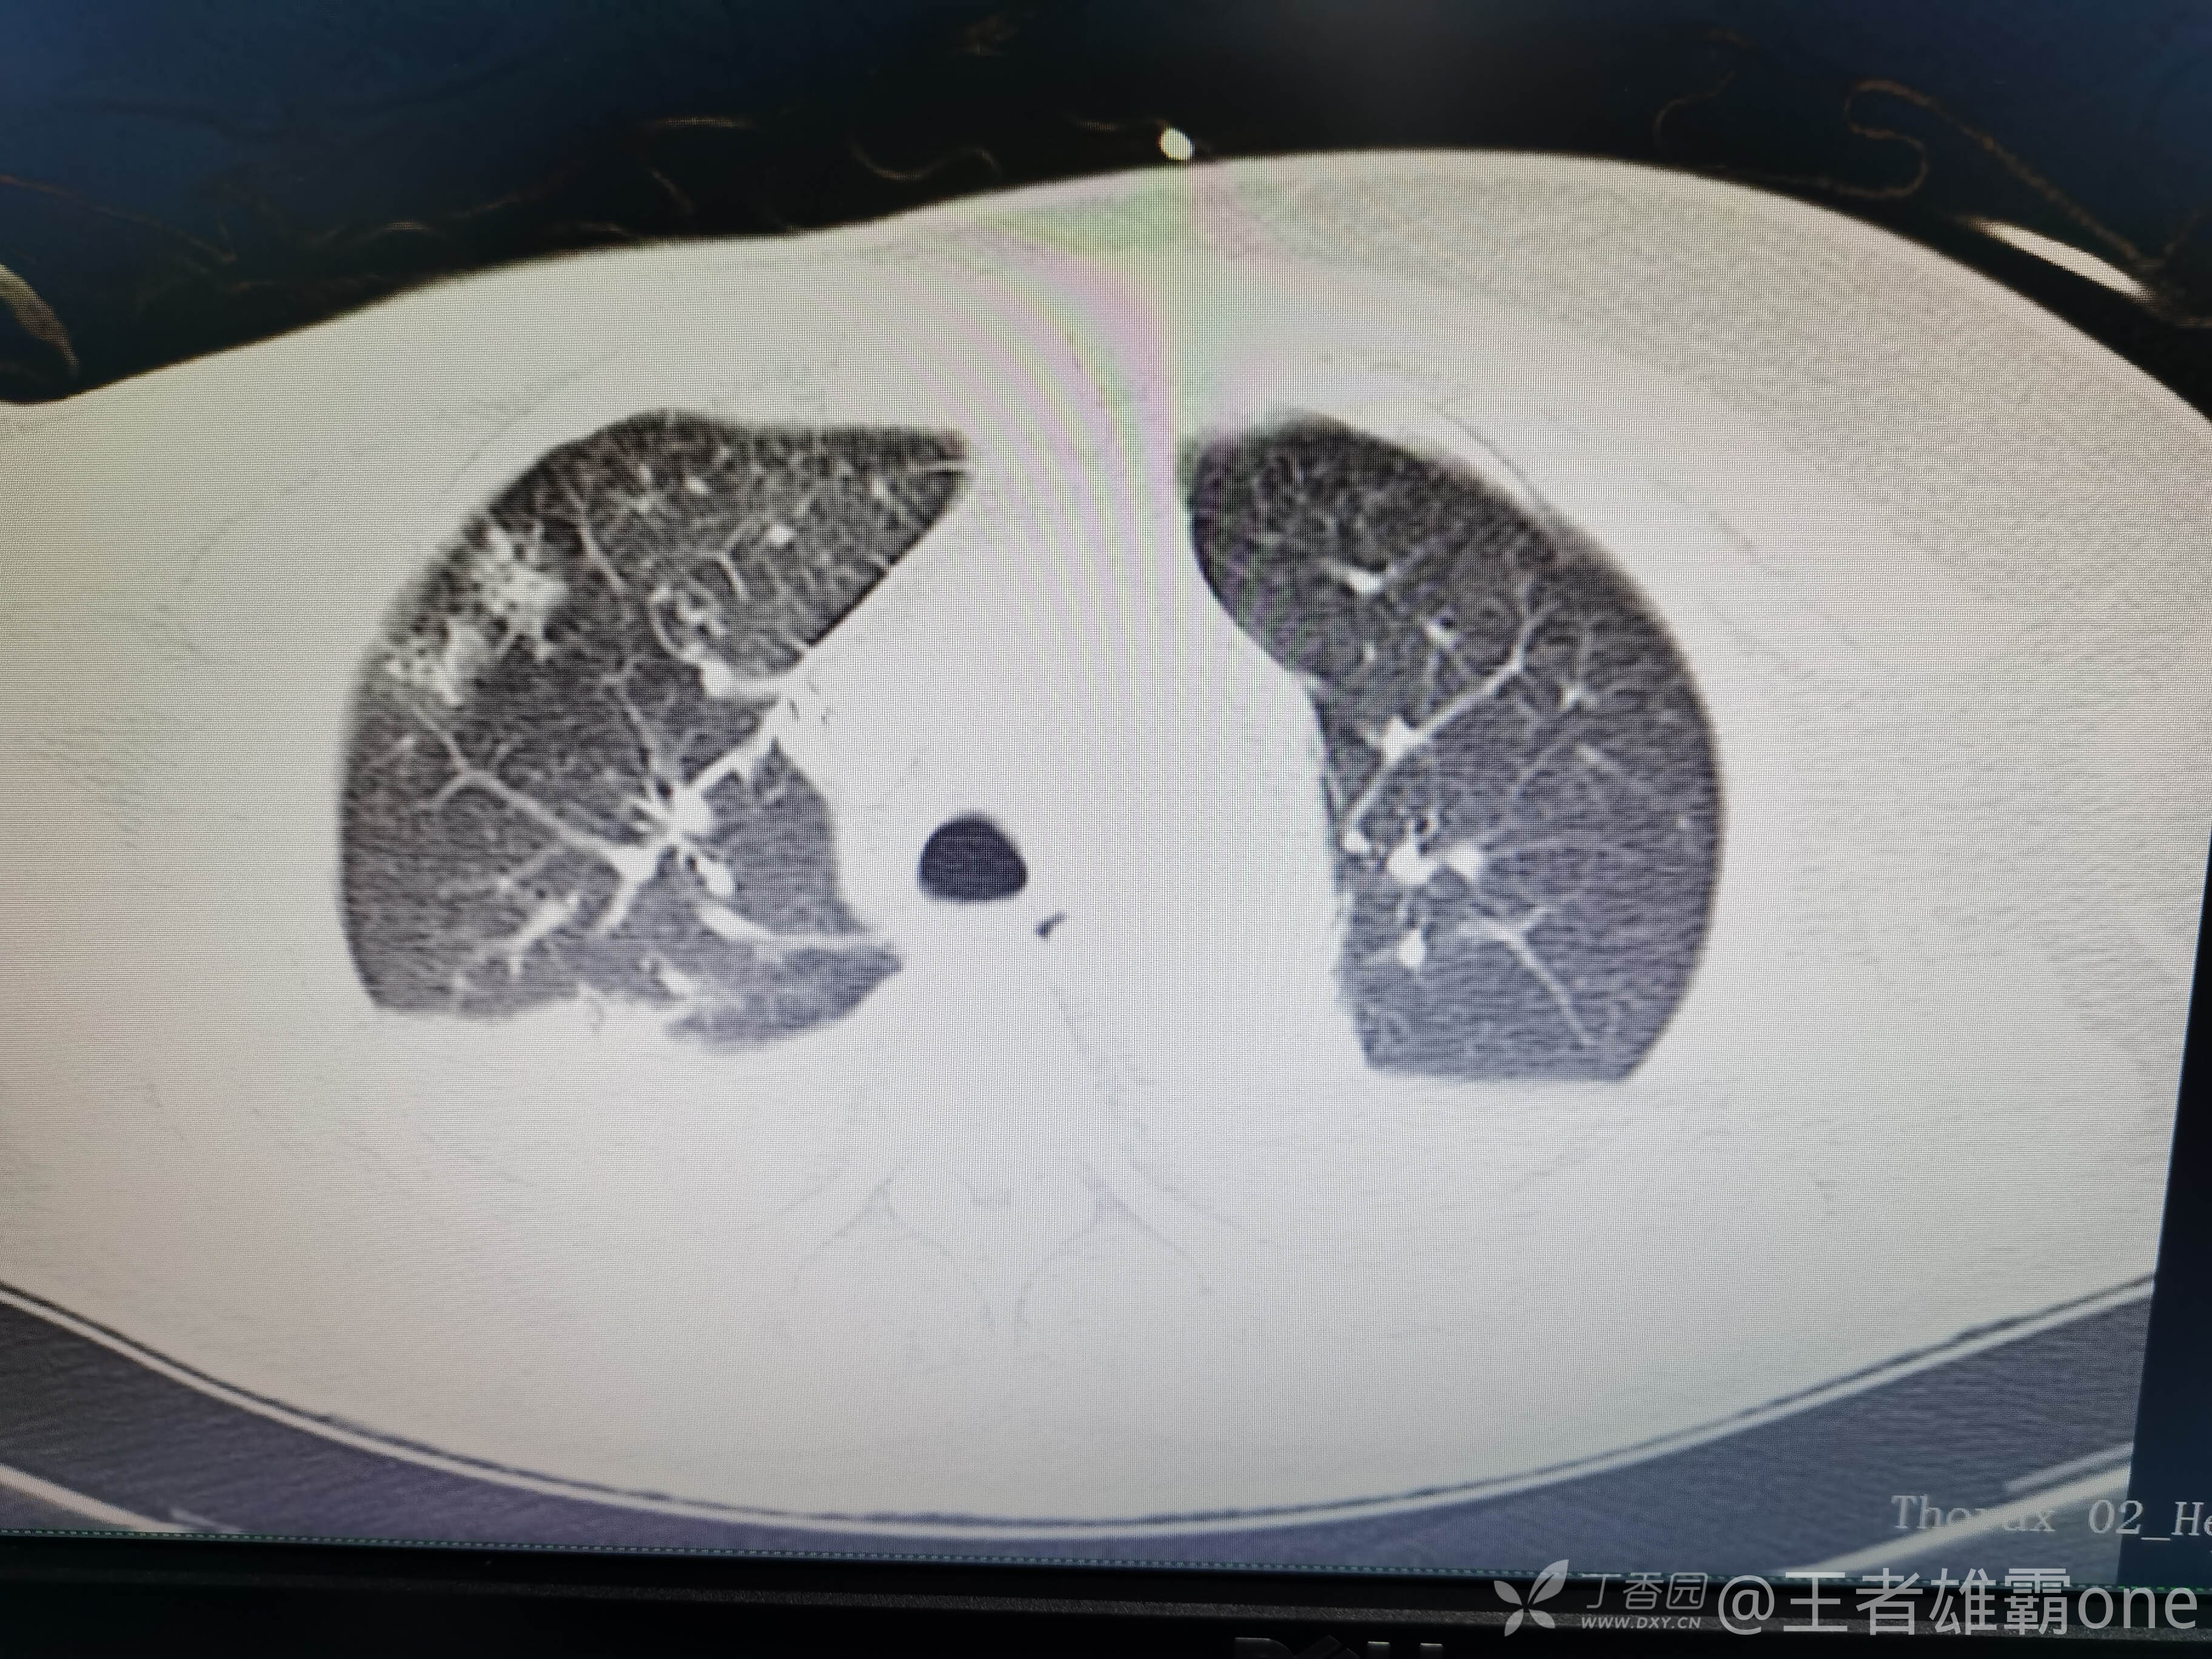

早上复查血常规:血红蛋白100g/L,白细胞11.1×109/L,血小板29×109/L。凝血功能:APTT37.9s,纤维蛋白原3.01g/L,凝血酶时间18.6s,D二聚体21530ug/L。生化:白蛋白36.2g/L,胆红素指标正常,谷丙56U/L,总胆红素38mmol/L,直接胆红素12.1mmol/L,谷草57U/L,肌酐91.1ummol/L,尿素13.97mmol/L,超敏C反应蛋白142.1mg/L。降钙素原17.70ng/ml。脑钠肽前体2164pg/ml。复查胸部CT:

那么问题来了,出现呼吸衰竭气管插管的病因是?请大家讨论分析!